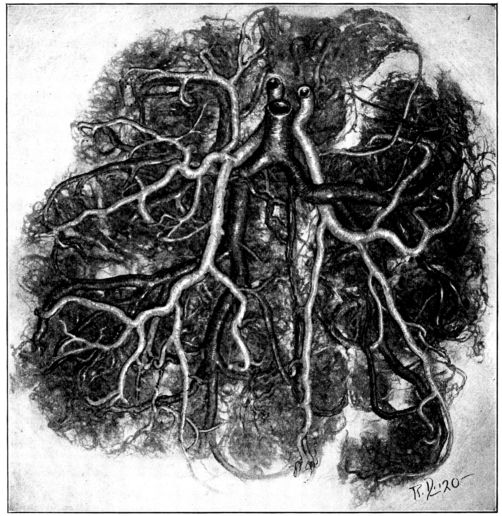

| 22. | Photograph of placental vessels | 72 |